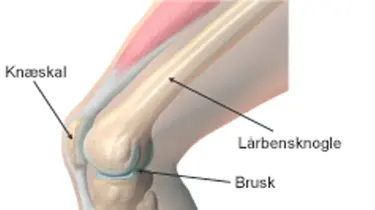

Knæskader og slid – få hurtig behandling

Knæsmerter kan opstå pludseligt efter en skade – eller udvikle sig over tid pga. slid, sport eller overbelastning. Hos Aleris står erfarne knæspecialister og fysioterapeuter klar til at hjælpe dig sikkert og hurtigt tilbage til et aktivt liv.

Ved hjælp af MR-scanning, røntgen og ultralydsscanning stiller vores speciallæger hurtigt en præcis diagnose. Det gør, at vi kan sætte ind med den rette behandling med det samme – uanset om det gælder sportsskader, slidgigt eller andre lidelser i knæet.

Aleris har er lang række erfarne idrætsspecialister, når det drejer sig om knæskader. De har stor erfaring med behandling af fx meniskskader, korsbåndsskader og ledbåndsskader.